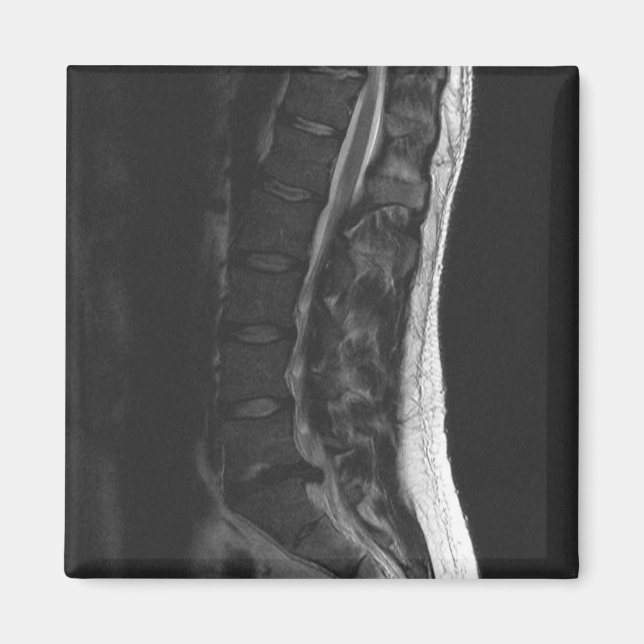

Transformei minha ressonância em uma imã de geladeira! Isto mostra o meu disco L5-S1 que foi interrompido. Isso sempre me lembrará de usar a postura adequada e dobrar aos joelhos! Não deixe que isso lhe aconteça... Eu fiz duas cirurgias para corrigi-lo.